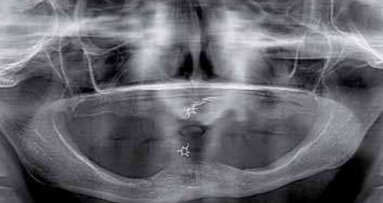

Badanie radiologiczne i kliniczne ujawniło torbiel w prawej zatoce szczękowej, zaniki kostne w wymiarze poziomym i pionowym regionach 14-16, 24-25, 36, 37 oraz 45. Rokowanie zębów #26, #27, #46, #44 określono jako niepewne, jednak nie zostały one zakwalifikowane do ekstrakcji.

W pierwszym etapie leczenia zaplanowano usunięcie torbieli w regionie 16-17. W kolejnym etapie implantację w pozycjach 14, 15, 16 z jednoczesnymi podniesieniem dna zatoki szczękowej metodą otwartą. W pozycjach 24, 25 zaplanowana została implantacja z jednoczesnym podniesieniem dna zatoki szczękowej metodą zamkniętą. Ze względu na stan sąsiednich filarów, podjęto decyzję o implantacji w regionie 45 i wykonaniu pojedynczej korony na implancie. Zdecydowano także o przeprowadzeniu procedury dwuetapowej ze względu na skalę zaniku kości w wymiarze pionowym. W regionie 34 oraz 36 i 37 również zaplanowano implantacje. Zaplanowano zaopatrzenie wszystkich istniejących filarów pojedynczymi koronami.

Po odwarstwieniu płata śluzówkowo-okostnowego w regionie 14-16 wypreparowane zostało okno kostne na przedniej ścianie zatoki szczękowej z użyciem frezu diamentowego. Po usunięciu torbieli rana została zaszyta szwami pojedynczymi.

W pozycjach 14 i 15 wprowadzone zostały implanty tytanowe AstraTech o średnicy śródkostnej Ø 4 mm, a w pozycji 16 o średnicy śródkostnej Ø 4,5 mm. Przestrzeń pod błoną Schneidera oraz fenestracja, jaka powstała od strony przedsionkowej pokryte zostały uprzednio pobranymi wiórami kości autogennej, materiałem BioOss oraz membraną resorbowalną BioGide. Ranę zaszyto szwami pojedynczymi.

W regionie 36 i 37 wprowadzono wszczepy tytanowe Astra Tech o średnicy śródkostnej Ø 4,5mm. W pozycjach 24 i 25 wprowadzone zostały implanty o średnicy śródkostnej Ø 4 mm z jednoczesnym podniesieniem dna zatoki szczękowej metodą osteotomową.